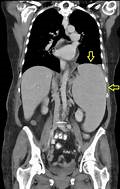

The patient's presentation is suggestive of splenic abscess, which is a rare but serious complication of splenomegaly. Splenic abscess is caused by bacterial or fungal infection of the spleen, usually from hematogenous spread or contiguous spread from adjacent organs. The most common symptoms are fever, chills, abdominal pain, and left shoulder pain (Kehr sign). The most significant laboratory finding is positive blood cultures, which indicate systemic infection and sepsis. Other laboratory findings may include leukocytosis, anemia, thrombocytopenia, elevated inflammatory markers, and abnormal liver function tests. However, these are nonspecific and may vary depending on the underlying cause of splenomegaly and the type of microorganism involved.